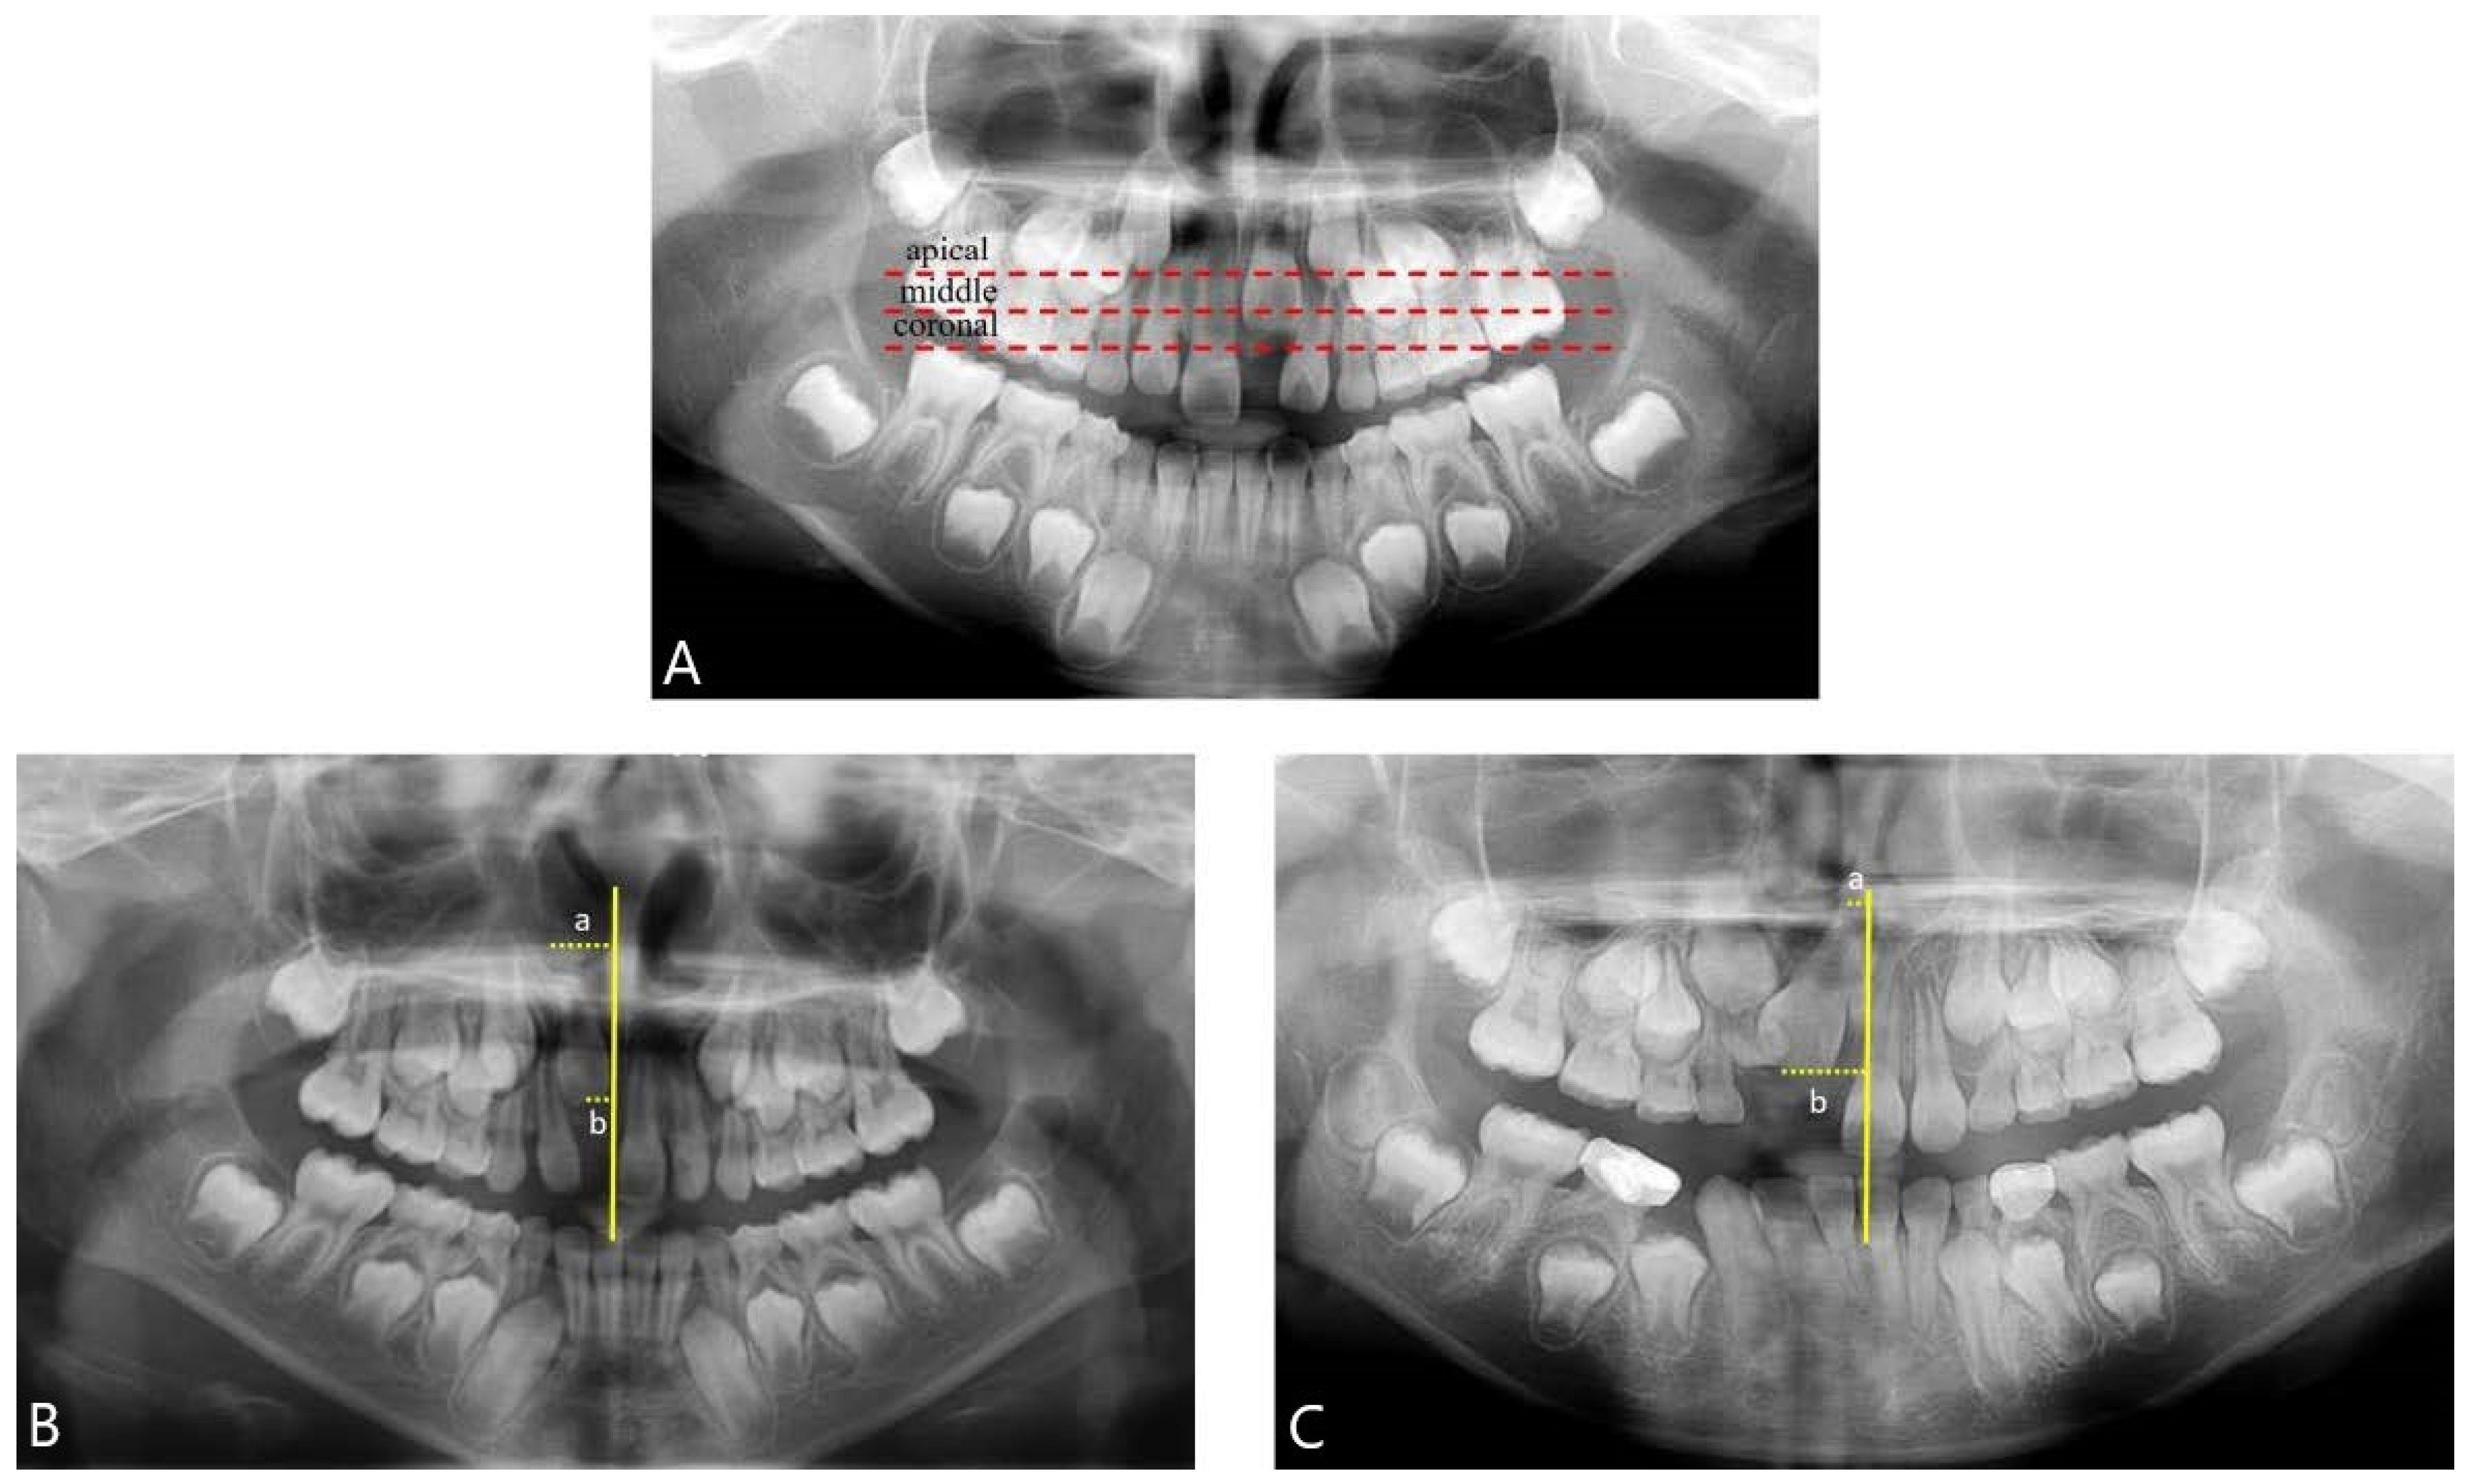

2.3. Panoramic Radiograph